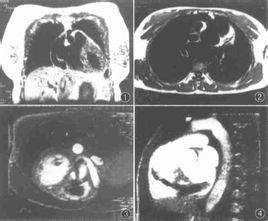

主動脈竇瘤破裂又稱佛氏竇瘤破裂,是由於主動脈竇壁缺乏正常的彈力組織和肌肉組織,受到高壓血流衝擊,逐漸形成囊狀瘤體,向外凸出、最終可導致破裂。此病為較少見的先天性心臟病。本病成年人發病率高,病情出現突然並發展迅速。

臨床表現主要有突然出現劇烈胸痛,心悸,氣促,並易引起心力衰竭。本病手術療效確切,手術死亡率低,術後可完全恢復正常心功能,但有嚴重心力衰竭手術死亡率高,術後恢復慢。因此,應早期手術。